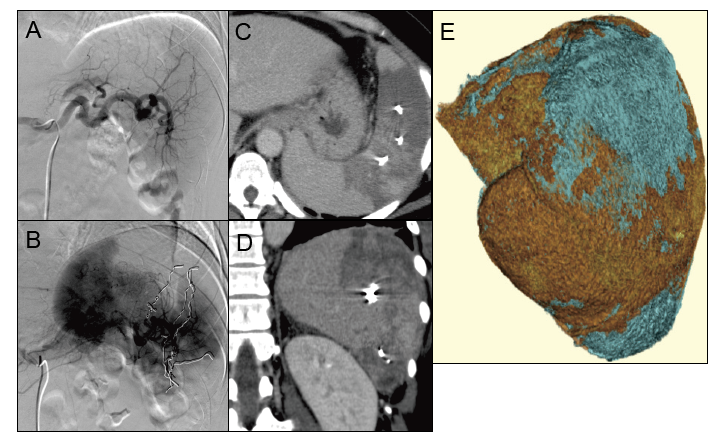

Partial splenic embolization (PSE) in Case 2

A:Before PSE

B:Microcoils were placed (two metallic coils in the superior branch 2, one in the mid branch 1, three in the mid branch 2, and three in the inferior branch).

C, D:Computed tomography (CT) on day +16 showed less intense enhancement of the embolized area than the non-embolized area. Mild splenic abscess was detected.

E:Three-dimensional image of the spleen. The red and blue areas indicate non-embolized (706.35 cc) and embolized (211.41 cc) areas, respectively. Post-PSE CT imaging revealed the embolization rate to be 23%.